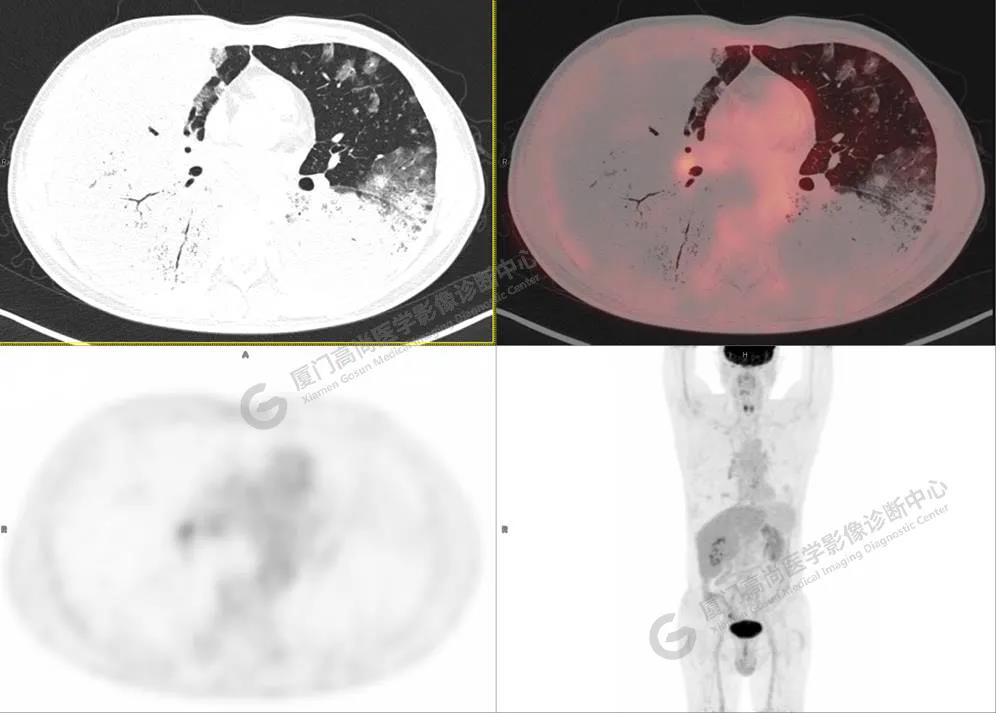

PET/CT影像圖

圖2

PET/CT所見(jiàn):雙肺大片實(shí)變影及磨玻璃影,部分呈地圖樣改變,累及右肺尖,部分放射性攝取輕微增高,SUVmax 1.77,其內(nèi)見(jiàn)多發(fā)支氣管充氣征象。

影像診斷: 雙肺大片實(shí)變影及磨玻璃影,大部分代謝不高,局部代謝輕微增高,考慮肺泡蛋白沉積癥,建議病理學(xué)檢查或肺泡灌洗物檢查。